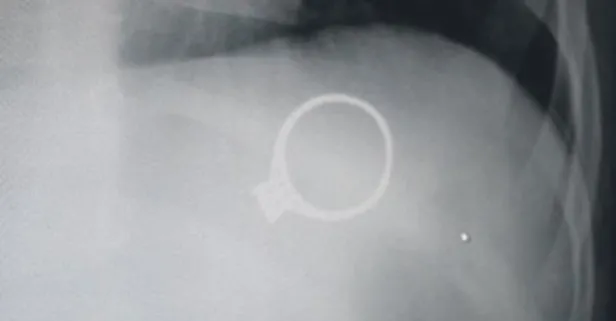

Sivas'ta, 1,5 yaşındaki M.G. isimli bebek, annesinin tek taş yüzüğünü yuttu. Yüzük 6 gün sonra doğal yolla çıktı. Çocukların bu tip cisimlere ulaşmasının önlenmesi gerektiğini söyleyen Op. Dr. Mahmut Aluç, "Yutulan cisim midesine düşmüştü. Kendiliğinden çıkmasını bekledik ve öyle de oldu. Çocuklar ağızlarına aldıkları her şeyi yutabilirler" diyerek aileleri uyardı.